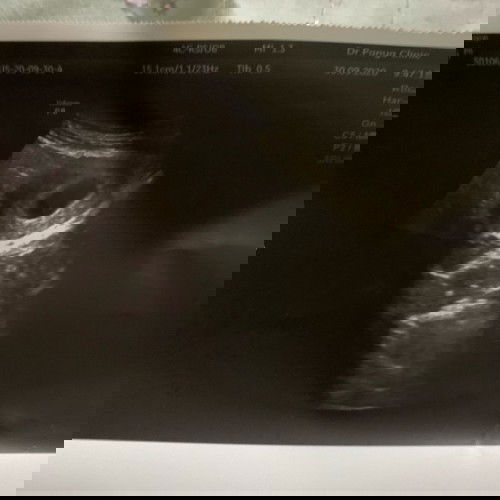

ท้องแรก หาหมอครั้งแรก คุณหมอบอกถุงใหญ่มากค่ะ แค่6 วีคเอง แต่ยังไม่เจอตัวน้อง รอลุ้นคุณหมอนัดรอบถัดไป #ขออย่าให้เป็นท้องลมเลย 🥺🥺